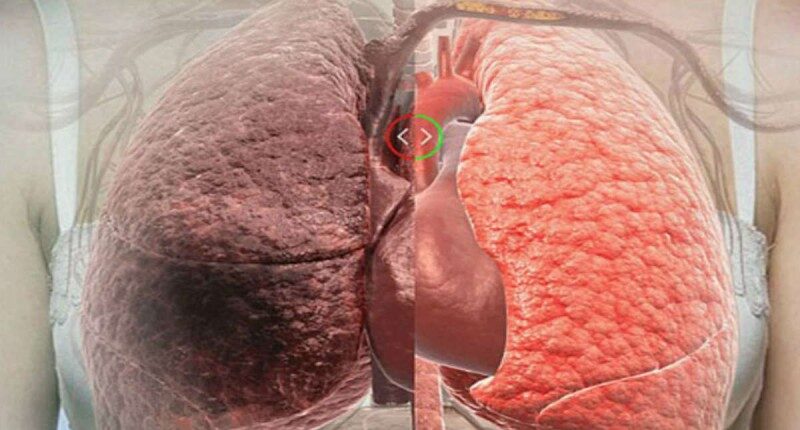

Η νικοτίνη προκαλεί ταχεία αύξηση της πίεσης του αίματος και σοβαρές βλάβες στους πνεύμονες. Επιπλέον, ακόμη και αν κάποιος σταματήσει το κάπνισμα, η επίδραση της νικοτίνης μπορεί να διαρκέσει για χρόνια.